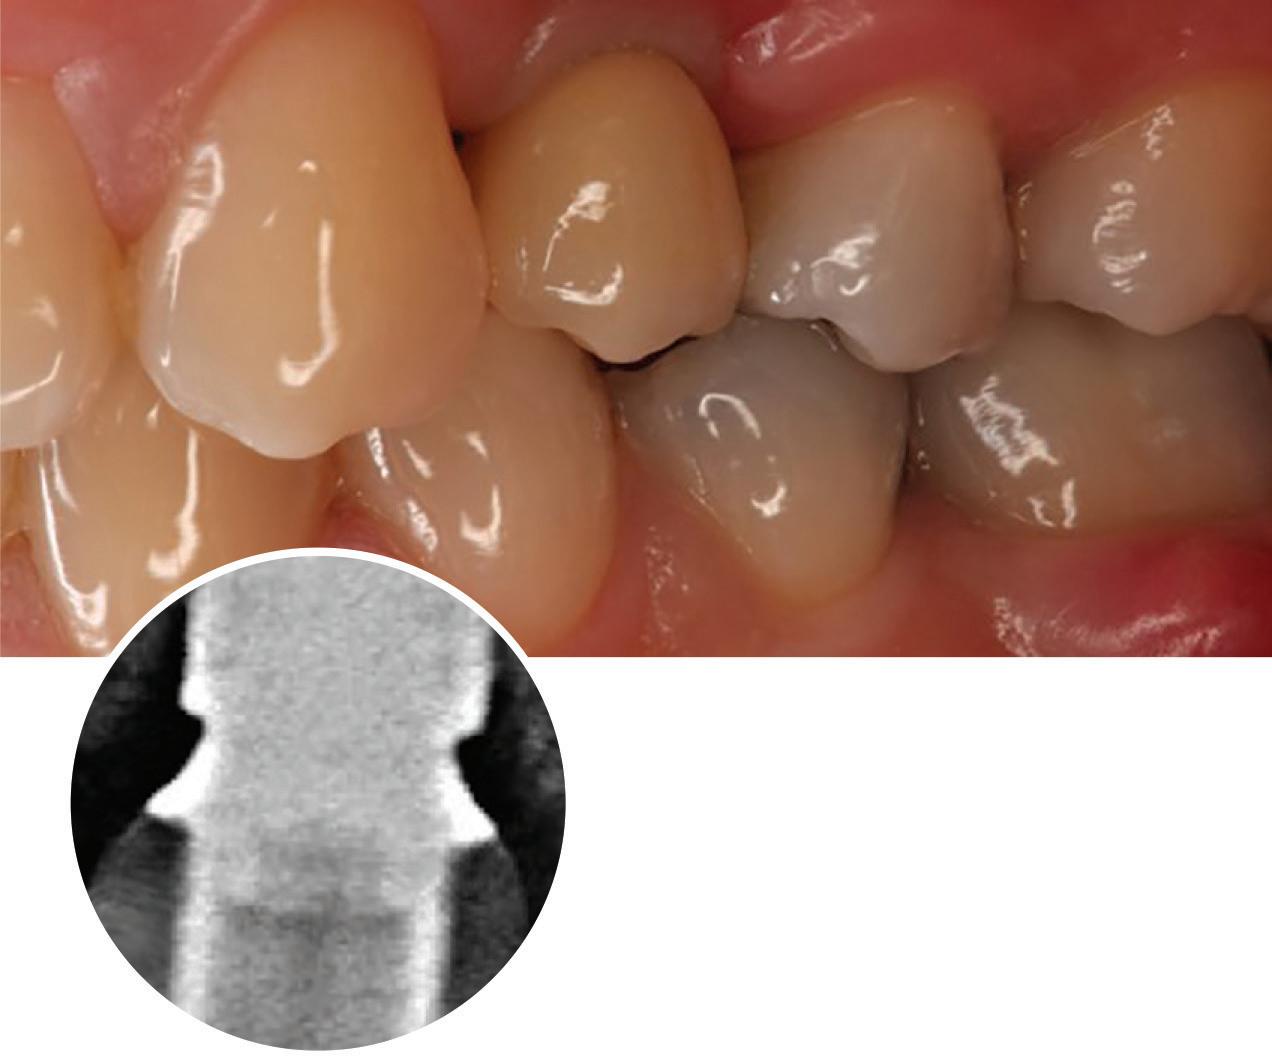

Figure 1: Radiographic Image of implants do not demonstrate bone loss due to the bisecting angle of the radiograph taken.

Figure 2: Radiographic image in a paralleling technique of implants dem onstrate moderate peri-implantitis with bone loss that will necessitate treatment.